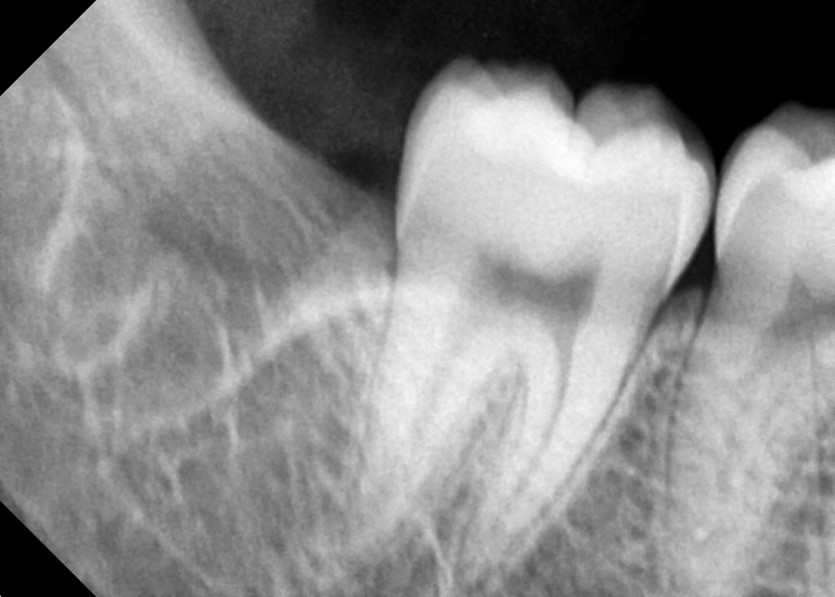

#18,28,38,48 사랑니 발치

구강 외과 전문의가 당일 발치했습니다.